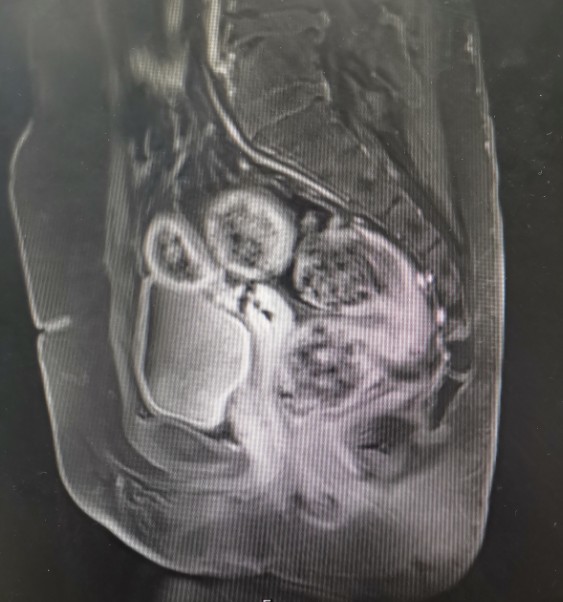

•全腹核磁:子宫术后改变,脂肪肝,双肾囊肿,盆腔少量积液。

轴位T1

轴位T2

矢状位T1

矢状位T2